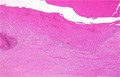

Macroscopic findings (left thalamic hemorrhage): A case of hypertensive hemorrhage ruptured into a lateral ventricle. Thalamic hemorrhage more marked than putamen hemorrhage due to its relatively high tendency of rupture to the ventricle.